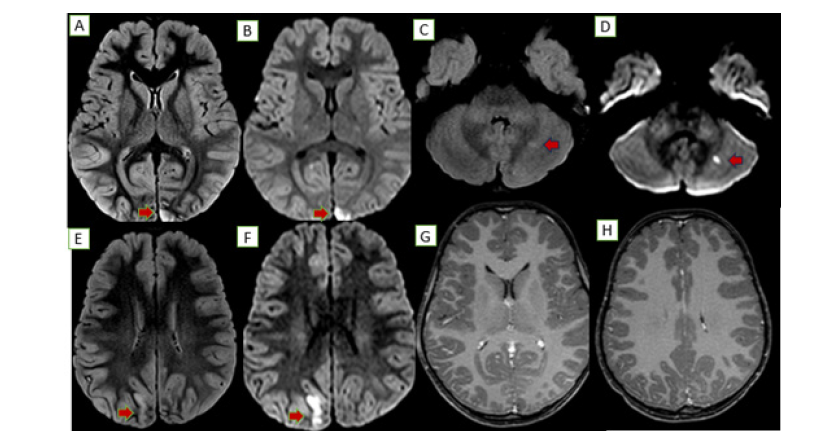

Figure 2:MRI PRE TREATMENT: Abnormal areas of nodular T2/FLAIR hyperintensities noted along the cortical and subcortical regions of bilateral occipital lobar regions (A, E) and left cerebellar hemisphere (C) with associated diffusion restriction in these areas (B, F, D). Post contrast MRI of the head, axial sections showed no significant enhancement/obvious thickening of adjacent meninges (G.H).

An MRI brain showed diffuse gyral edema with T2/FLAIR hyperintensities and diffusion restriction in the bilateral occipital lobes and a tiny focus in the left cerebellar hemisphere (Figure 2). Serology revealed an intermediate positive Brucella IgM and a negative scrub IgM. A CSF analysis showed 110 cells, sugar of 71mg/ dL, and protein of 34mg/dL. Further tests revealed a significantly low serum B12 (158pg/mL), elevated homocysteine (98.7μmol/L), and a high ESR (102mm/hr). The child became afebrile with initial therapy. The confirmation of Brucella exposure led to the addition of septran and rifampicin for a definitive diagnosis of neurobrucellosis. By day 4, her sensorium improved, and she was started on injectable B12 for the deficiency and Vitamin D for associated rickets. She improved gradually on a Rifampicin based triple-drug regimen for 45 days. A follow-up MRI showed residual T2/FLAIR hyperintensities with subtle atrophy but no diffusion restriction, indicating resolved acute inflammation (Figure 3).